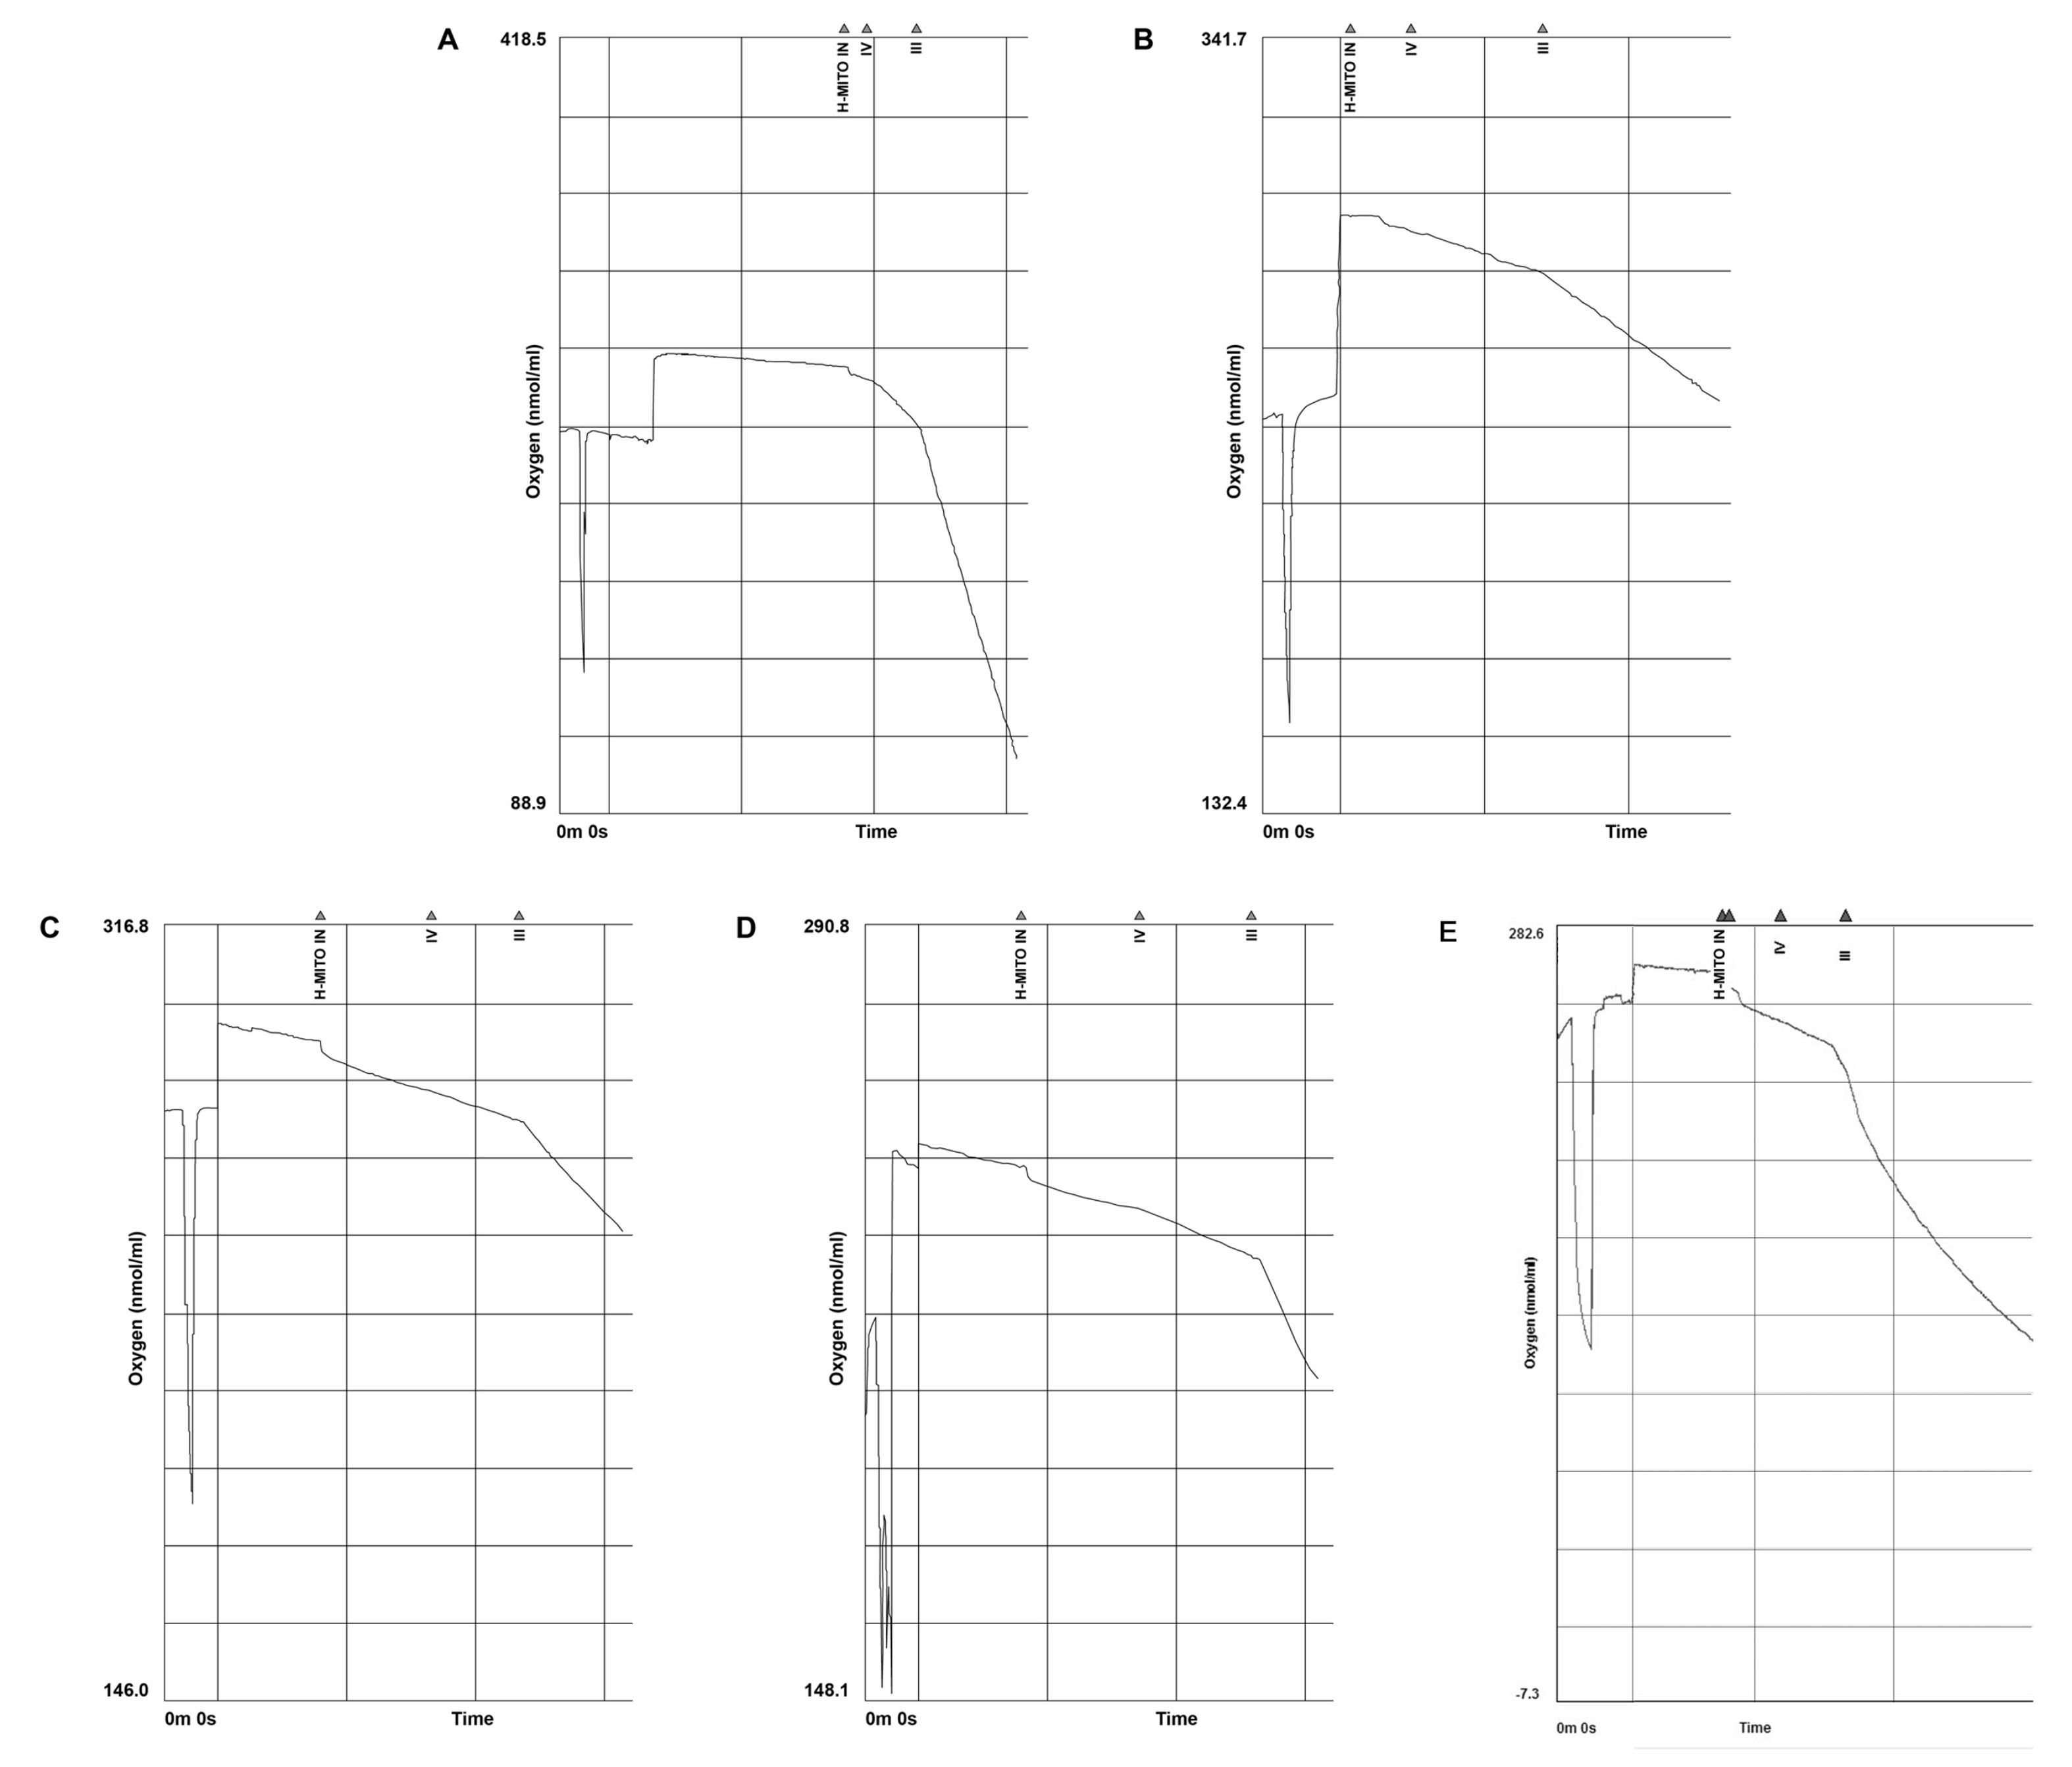

1.2.5 心肌线粒体的分离及呼吸功能的测定心脏摘取后1 h内进行相关检测,标本浴于0~4 ℃冰水中。采用动物组织线粒体分离试剂盒(南京碧云天生物科技公司)分离心肌细胞线粒体,线粒体呼吸控制率(respiratory control rate,RCR)检测试剂盒(美国 GENMED SCIENTIFICS公司)检测心肌细胞线粒体的RCR。心肌组织称质量后放入预冷的Dounce匀浆器,加入线粒体分离介质,匀浆后取上清夜。差速离心法(德国 eppendorf 公司)最终获取沉淀,即为提取的线粒体,分离介质重悬线粒体,置于冰槽保存待检。呼吸功能的检测采用Clark氧电极法(Oxytherm 液相氧电极,英国 Hansatech)[5]。室温下校正后,反应槽内加入2.5 mL介质液,基线平稳后开始记录。加入20 μL线粒体悬液,1 min后加入Ⅲ态底物液,测得氧消耗率为Ⅲ态呼吸(R3) ,2 min后加入Ⅳ态底物液,测得氧消耗率为Ⅳ态呼吸(R4) 。线粒体呼吸控制率(RCR)= R3/R4。

与Sham组比较,PR 4 h 心肌细胞线粒体的Ⅲ态呼吸速率及RCR明显下降(均P<0.05) ;PR 12 h和 24 h呼吸功能逐步恢复,仍低于Sham(均P<0.05) ;PR 72 hⅢ态呼吸速率及RCR与Sham组比较,组间差异无统计学意义(均P>0.05) 。复苏后各组Ⅳ态呼吸速率与Sham组比较,差异无统计学意义(P>0.05) (表 3,图 5)。

| A:sham组(n=3) :B:PR 4 h组 (n=8) ;C:PR 12 h组(n=7) ;D:PR 24 h组(n=6) ;E:PR 72 h组(n=5) ;H-MITO IN,线粒体加入的时间标记;Ⅳ,Ⅳ态呼吸,即ADP耗尽后耗氧速率;Ⅲ,Ⅲ态呼吸,即ADP加入后耗氧速率 图 5 Clark氧电极描记线粒体耗氧率曲线图 Figure 5 Representative traces of oxygen consumption of isolated mitochondria by a Clark oxygen electrode |